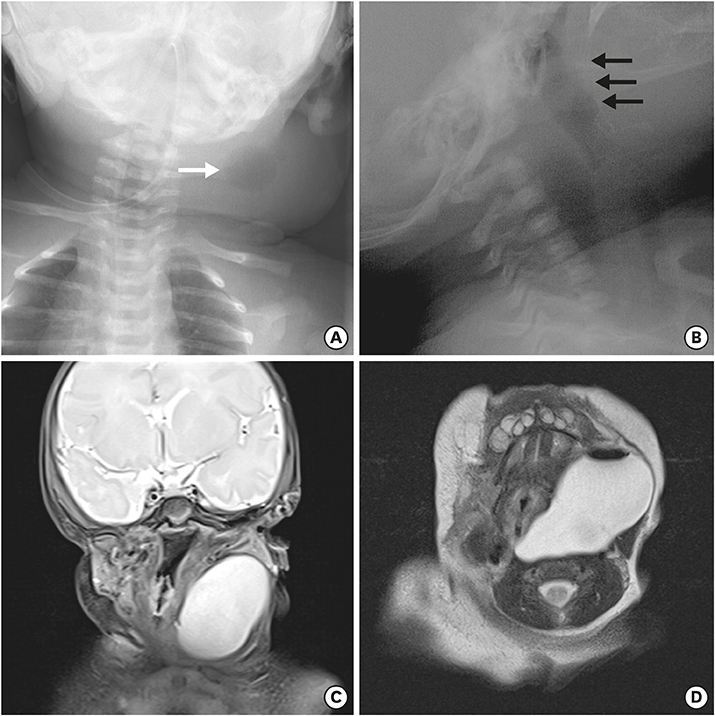

Fig. 4

Surgical dissection of pyriform sinus cyst and fistula (black arrow) ligation was done.

A newborn female infant, gestational age of 39+2 weeks, and 3.46 kg at birth was referred to our NICU due to a 7 cm sized left neck mass presented at birth. No significant medical history during antenatal care was noted. The baby arrived at our NICU 3 hours after birth and physical examination revealed a soft, tense, movable 7 cm long mass without signs of inflammation. Initial neck X-ray showed a 4.7×3.9 cm sized soft tissue density mass at left side of the neck containing round air density (Fig. 3A). With experience of patients with pyriform sinus cysts, gastric tube feeding was initiated from day 1. A sonographic study of the neck mass revealed findings consistent with pyriform sinus cyst, located at the medial side of the left carotid artery and extending to the posterior aspect of the left thyroid gland. The cyst was unilocular and contained isoechogenic debris. Esophagography showed a small tubular opacity from the left pyriform sinus adjacent to the air-filled cyst, suggesting a fistula (Fig. 3B). On neck magnetic resonance imaging (MRI), the fistula was not visualized but a cyst of homogeneous signal intensity without wall thickening or enhancement was visualized with air-fluid level, suggesting communication with the esophagus (Fig. 3C and D). On the 6th day of admission, pyriform sinus cyst resection and fistula ligation was done (Fig. 4). The size of the cyst was 7.0×3.5 cm on operation findings. Histological results of the dissected cyst were negative for malignancy and showed many benign squamous epithelial cells with some multinucleated histiocytes and mixed inflammatory cells. There was no intra-operative complication and the patient recovered uneventfully. Bottle feeding was initiated on postoperative day 7 and the patient was discharged 10 days after surgery.